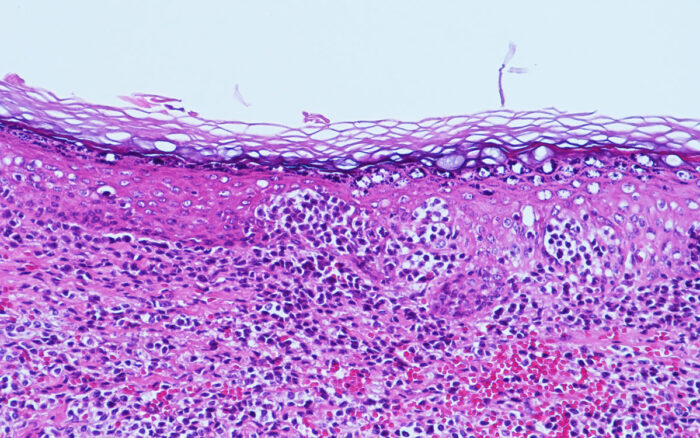

Laboklin: Meerschweinchen: Haut, epitheliotropes T-Zell-Lymphom, Hämatoxylin-Eosin (HE) -Färbung

Pathohistologische und zytologische Untersuchungen beim Kleinsäuger – Möglichkeiten und Grenzen

Tumor- und Infektionsdiagnostik beim Kleinsäuger mittels Zytologie und Histopathologie – auch Spezialfärbungen und Immunhistologie sind bei Laboklin etabliert